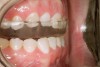

Figure 13  Adolescent triad: A 16-year-old with pathologic wear on incisors and a loss of tooth texture from erosion and abrasion. Medical history was indicative of the triad.

Figure 13